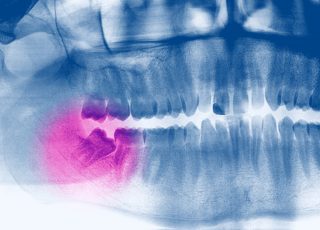

Parmi les urgences dentaires que nous rencontrons souvent en clinique, on retrouve l’abcès dentaire. C’est une condition qu’on doit traiter sans attendre, vu la douleur qu’un abcès engendre et les complications qui peuvent en découler. L’équipe Prisma Dentistes vous présente donc des informations importantes au sujet de l’abcès dentaire, de symptômes qui y sont associés, ainsi […]